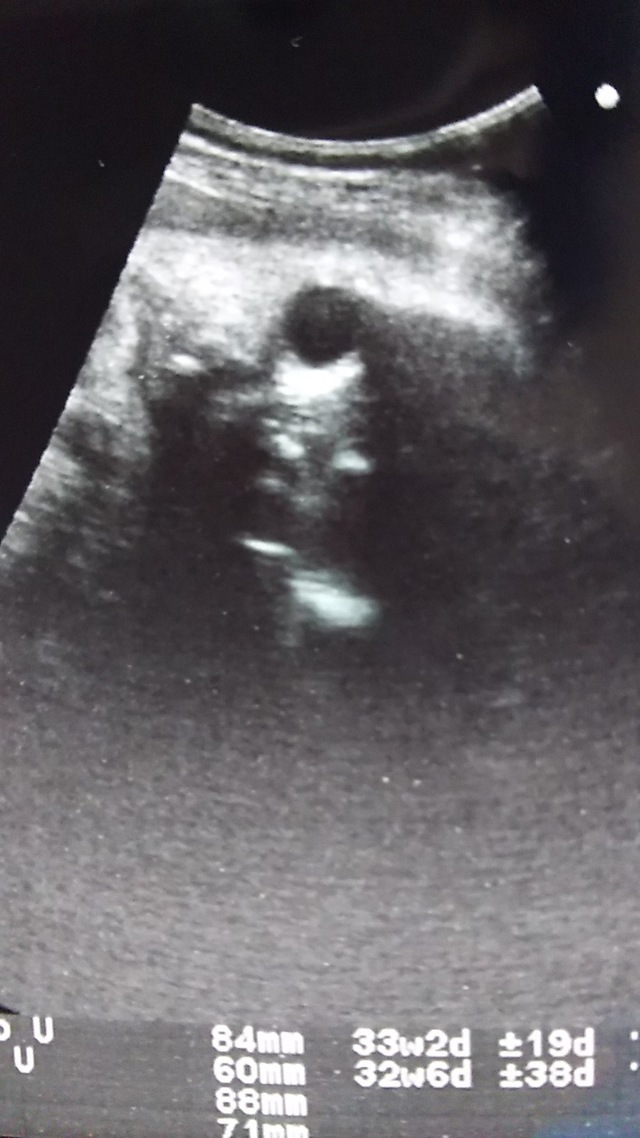

33週5日(33w5d・男の子)|みーひろ916 さん(30歳)

エコー写真撮影時のエピソード:

男の子と完全にわかる写真。 分かってはいましたが、もう一度先生に聞きました。 お顔が見えなかったのが残念です。

赤ちゃんが大きすぎるみたいで、なるべく早く産めるように頑張らないとしんどいと言われたので、里帰りしたらいっぱい体を動かして早く降りてくるように頑張ります。